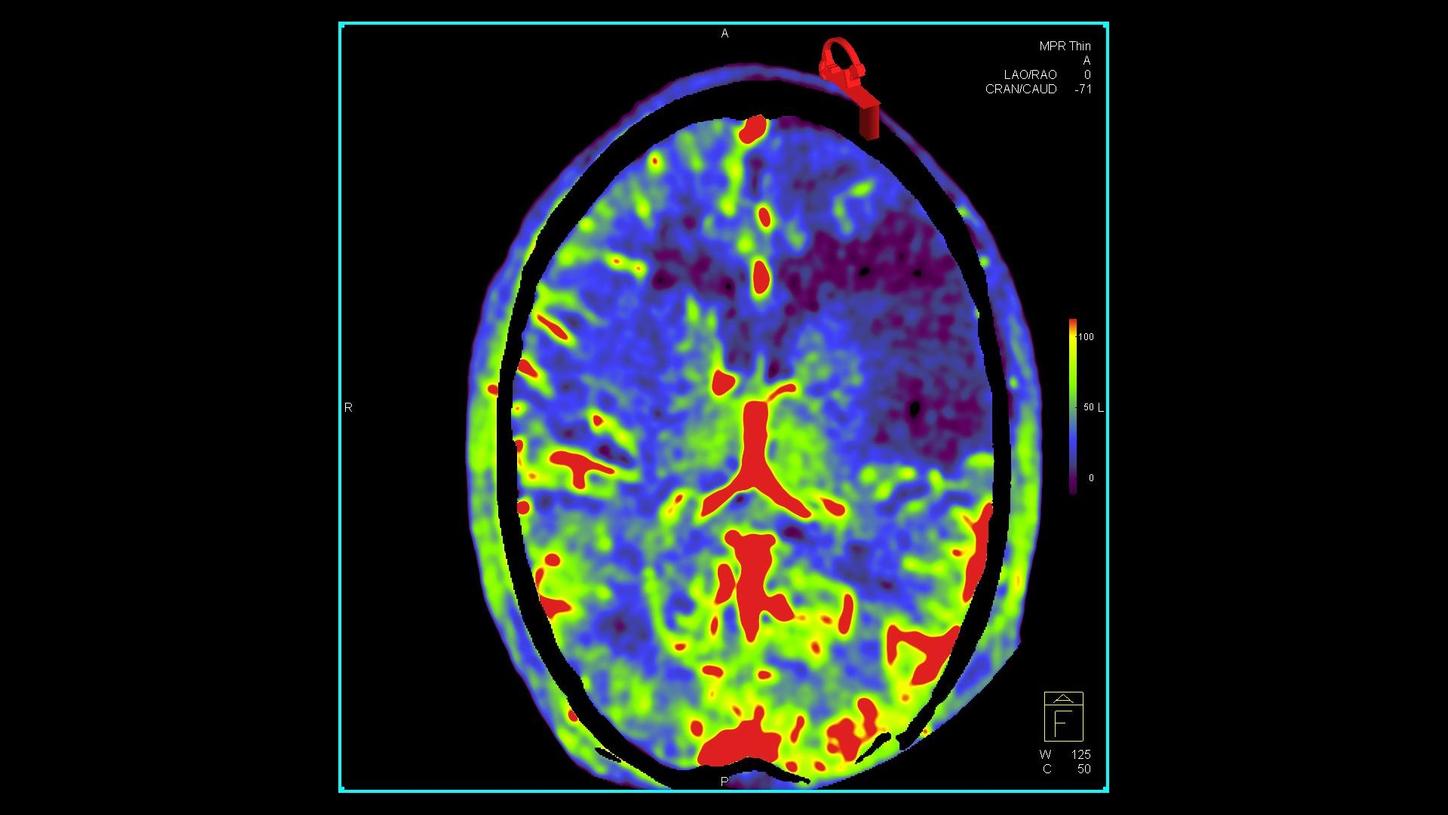

A new approach to image quality and dose in minimally invasive interventions

During a procedure, interventionalists and surgeons have to see clearly – while keeping dose as low as possible. Based on big data, OPTIQ delivers constant image quality throughout a procedure, independent of angulation or patient size1,2, while also significantly reducing dose.